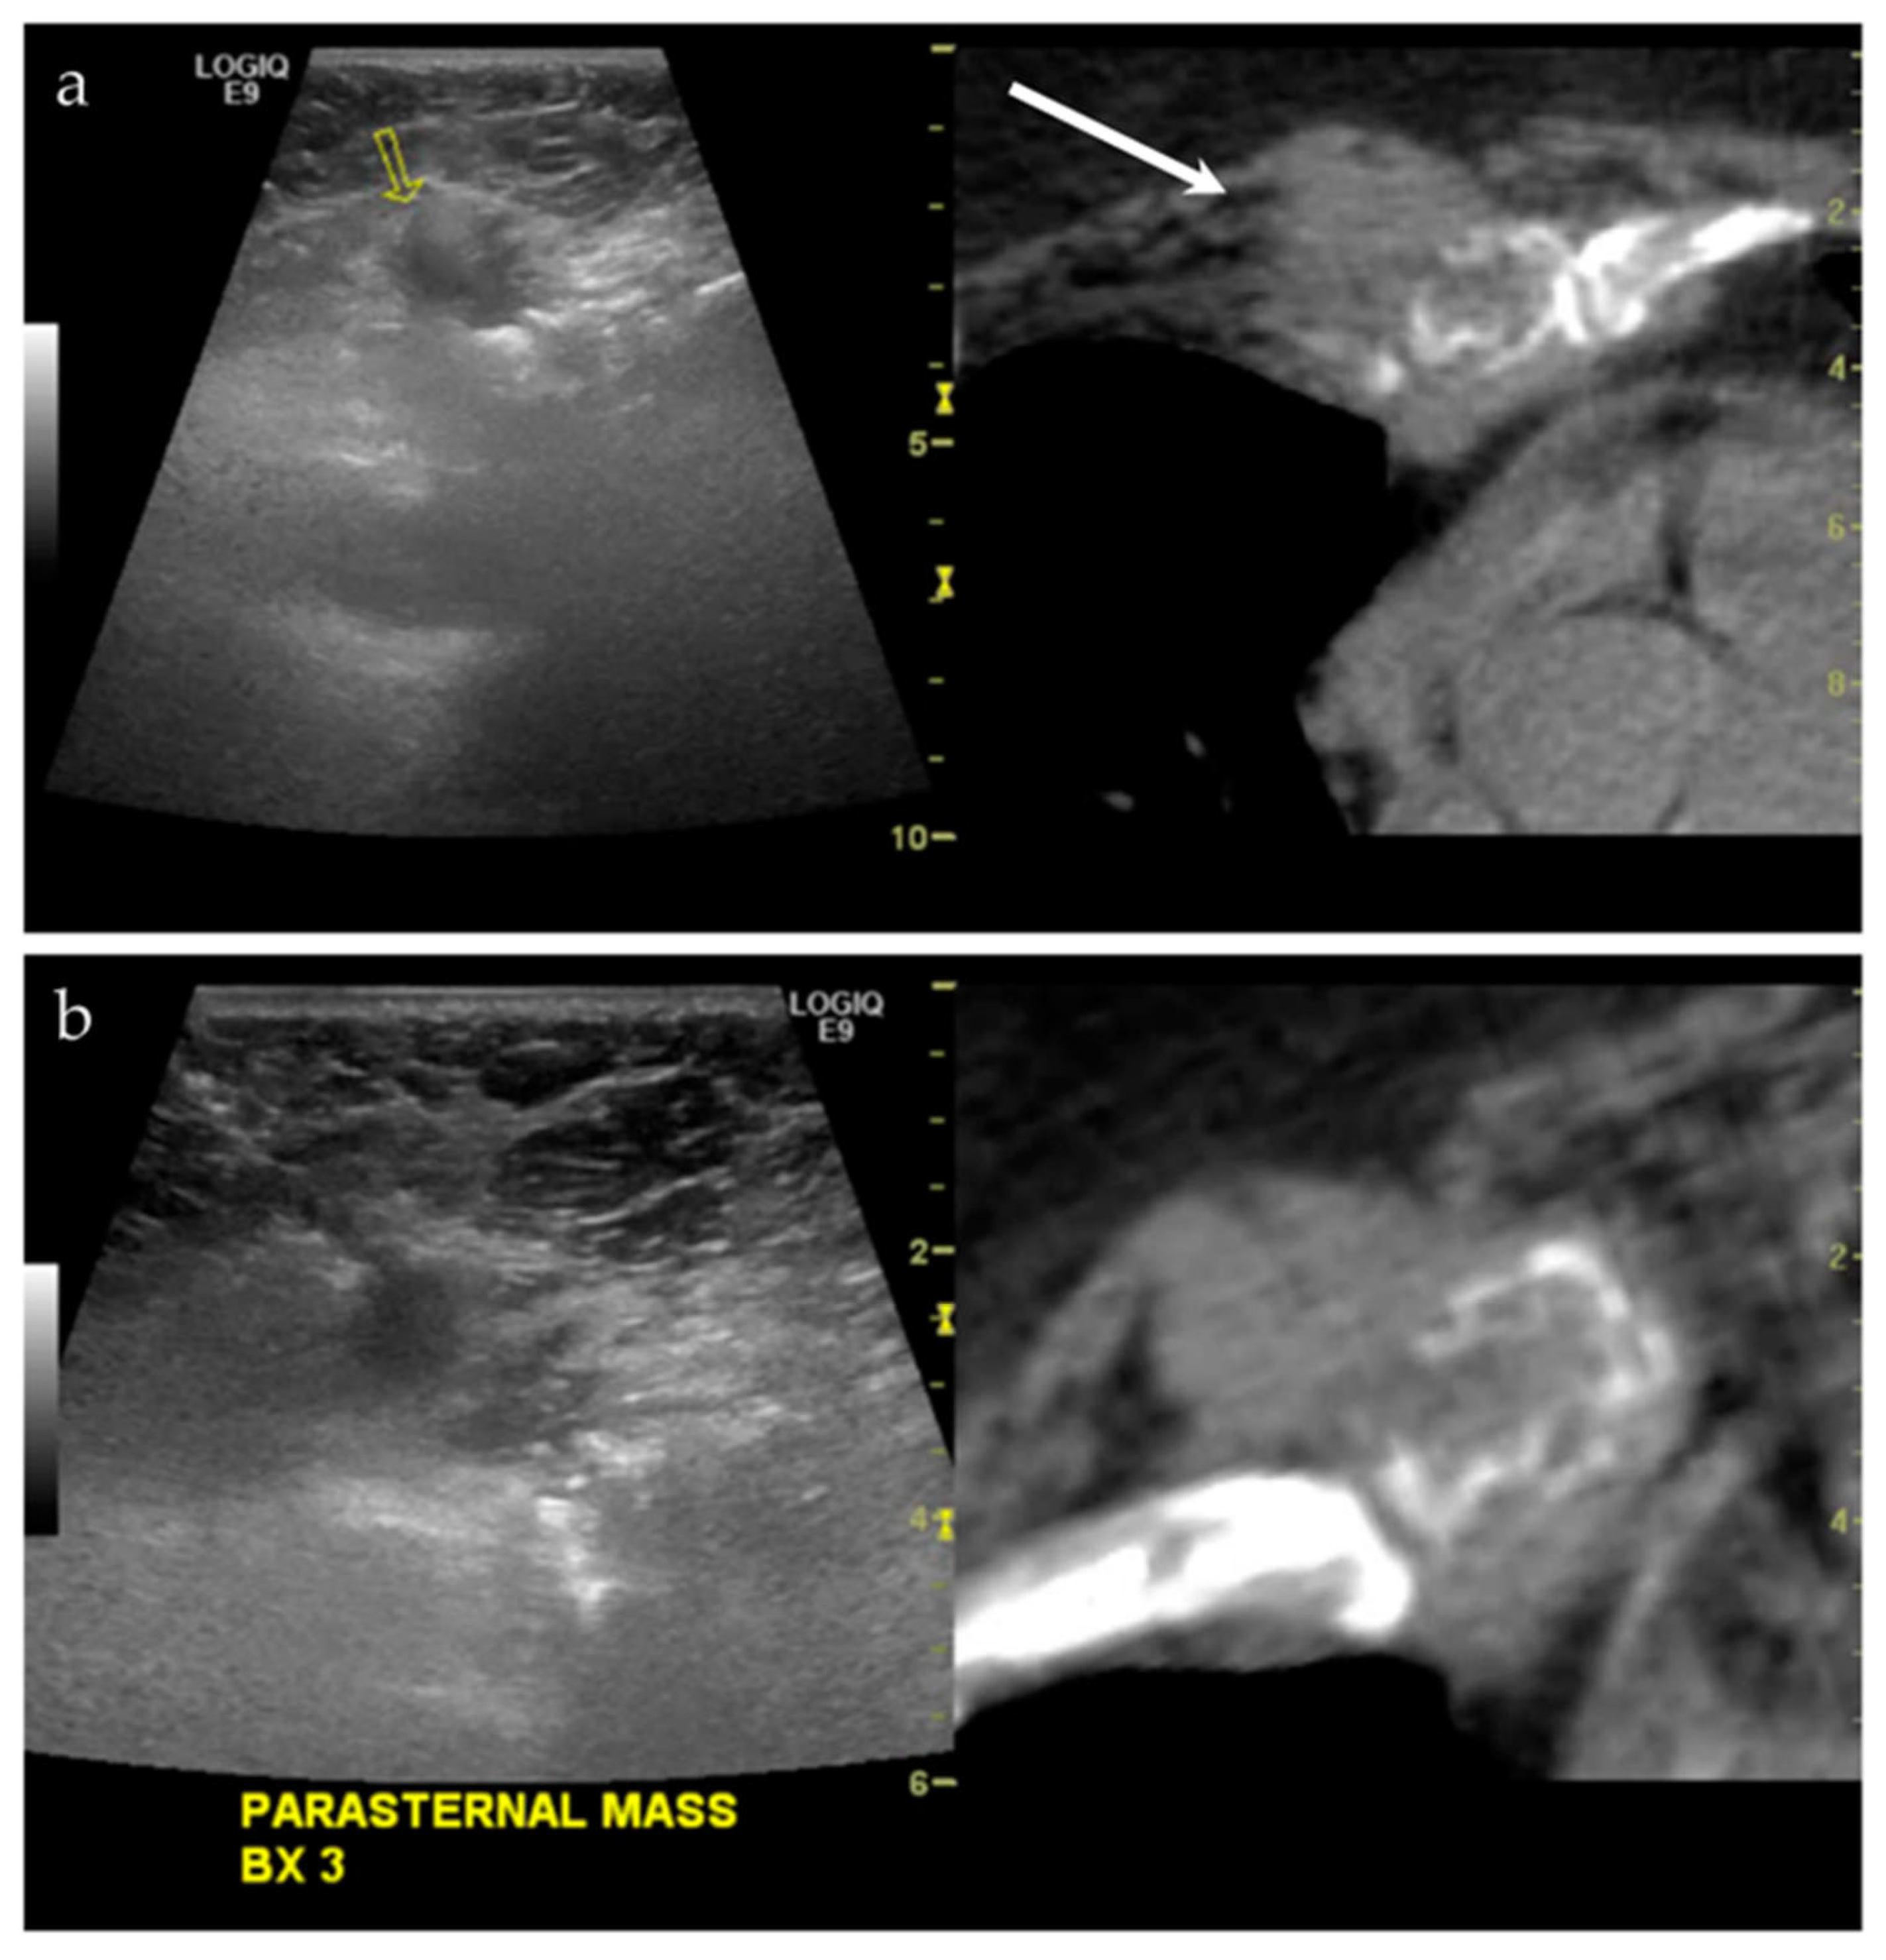

3.2.4. Targeted Percutaneous Lesion Biopsy and/or Aspiration

| NA/F | Right parasternal region | US-CT | Metastatic disease, lung adenocarcinoma | Neoplastic, malignant |